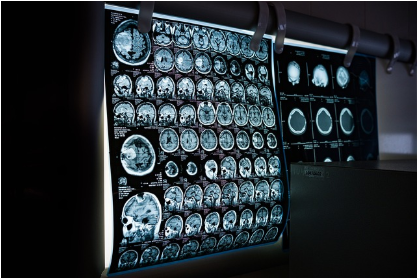

현대 의학 진단에서 빼놓을 수 없는 핵심 장비인 CT(컴퓨터 단층 촬영기)는 우리 몸속을 정밀하게 영상화하여 질병을 진단하는 데 혁명적인 변화를 가져왔습니다. CT 시스템은 X선을 생성하는 장치, 환자를 이동시키는 테이블, 방대한 데이터를 처리하는 컴퓨터까지 여러 복잡한 부품들이 유기적으로 결합되어 작동합니다. 이 모든 필수 구성 요소들 중에서 단 하나를 꼽아 '가장' 중요한 부품이라고 말할 수 있을까요? 여러 의견이 분분할 수 있지만, 많은 의료 영상 전문가들은 그 답으로 주저 없이 '검출기(Detector)'를 지목합니다.

왜 CT 검출기가 CT 시스템에서 가장 중요한 부품으로 평가될까요? 다른 필수 부품들도 많은데 말이죠. 검출기가 CT의 심장과도 같은 위치를 차지하는 근본적인 이유를 이 글에서 자세히 알아보겠습니다.